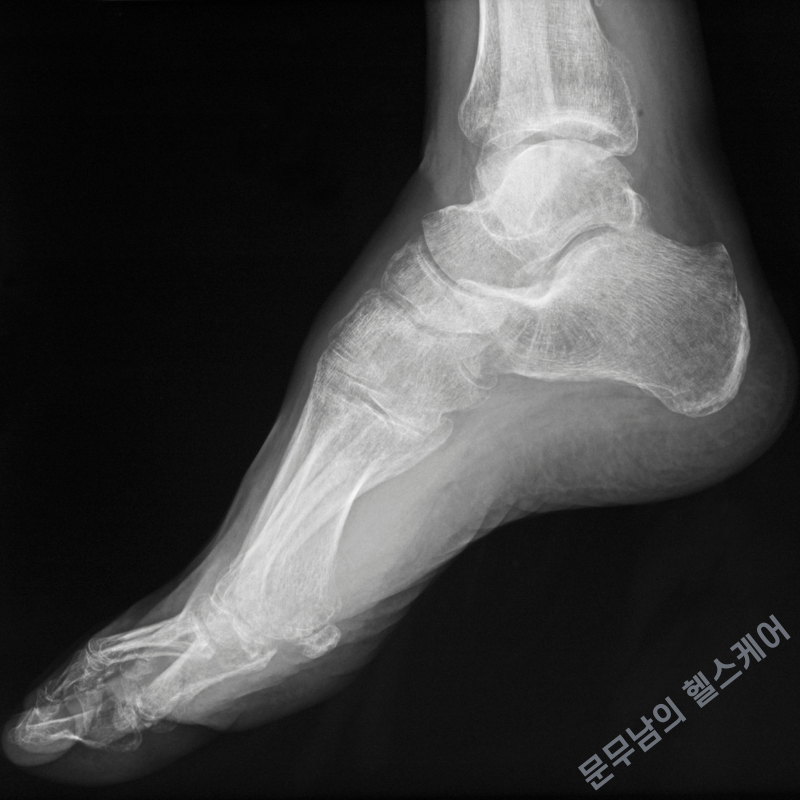

요족이라는 것은 기본적으로 발등이 정상보다 높이 올라와 있는 상태를 의미합니다. 옆에서 보았을 때는 발바닥의 아치가 높아서 발바닥이 위로 오목하게 올라간 것처럼 보이곤 하지요.

이런식으로 지나치게 높은 아치발 형태는, 체중이 발바닥 전체에 골고루 분산되지 못하게 하여 체중이 발뒤꿈치나 앞꿈치 방향으로 쏠리게 합니다. 이러한 상태는 곧 여러가지 근골격계 질환들을 유발하게 됩니다.

일반적으로 정상적인 발모양을 가지고 있는 사람들은 어느정도 발뼈의 아치각을 형성하는 것이 정상이지만, 아치각이 지나치게 커지게 되면 체중이 발바닥 전체에 골고루 분산되기가 어려워집니다. 따라서 보행장애가 발생하는 경우들도 종종 발생하게 됩니다.